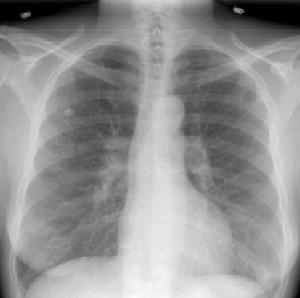

(三)心脏X线表现 酷似二尖瓣病变的表现,两肺野郁血,心界呈轻度到中度增大,主要表现为左心房和右心室扩大,食管钡餐检查可见到食管轻度到中度的压迹。